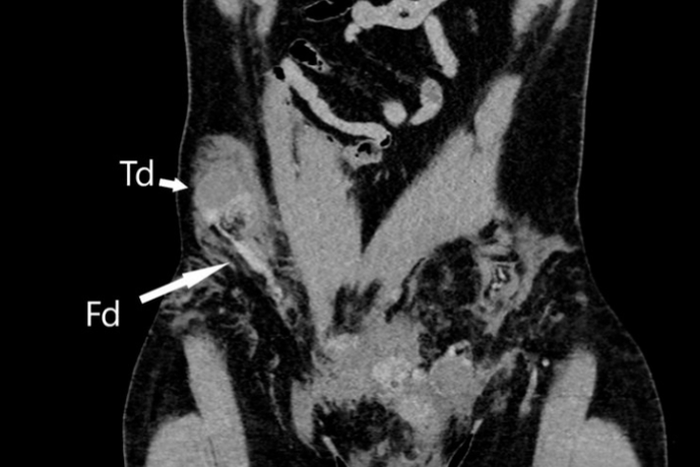

Après avoir réussi à maîtriser l'hémorragie et stabiliser le patient, les médecins se sont penchés sur le cas particulier de la disparition d'un testicule. Des examens médicaux approfondis ont révélé que le testicule droit du patient s'était retrouvé dans son abdomen à la suite de l'impact, où il avait été poussé à travers le canal inguinal, une structure de 4 à 6 cm de long reliant l'abdomen au scrotum. Ce cas extraordinaire a été documenté dans un rapport publié dans le prestigieux BMJ Case Reports.

La luxation testiculaire, bien que rare, est une complication connue chez les hommes ayant des accidents de moto, en particulier chez ceux dans la vingtaine. Cependant, la migration du testicule vers l'abdomen ne survient que dans environ 6 % des cas, ce qui rend ce cas particulièrement exceptionnel.